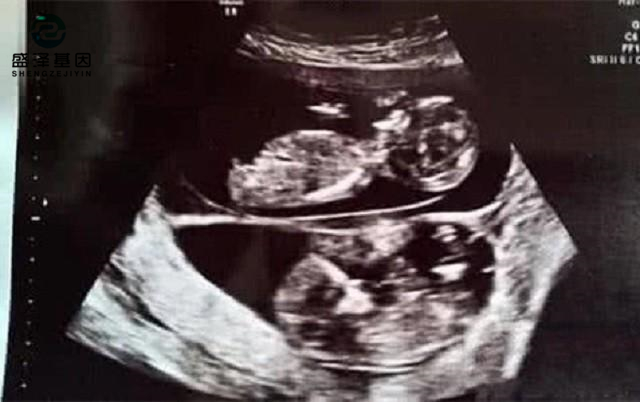

有個女的跟老公做了3次試管嬰兒,失敗了兩次,第三次卻意外成功。

女方就拉著老公來做產前親子鑒定。

鑒定結果:胎兒不是老公的。

親子鑒定師拿她公公的檢材去化驗,結果很明顯:

匹配度99.99%。